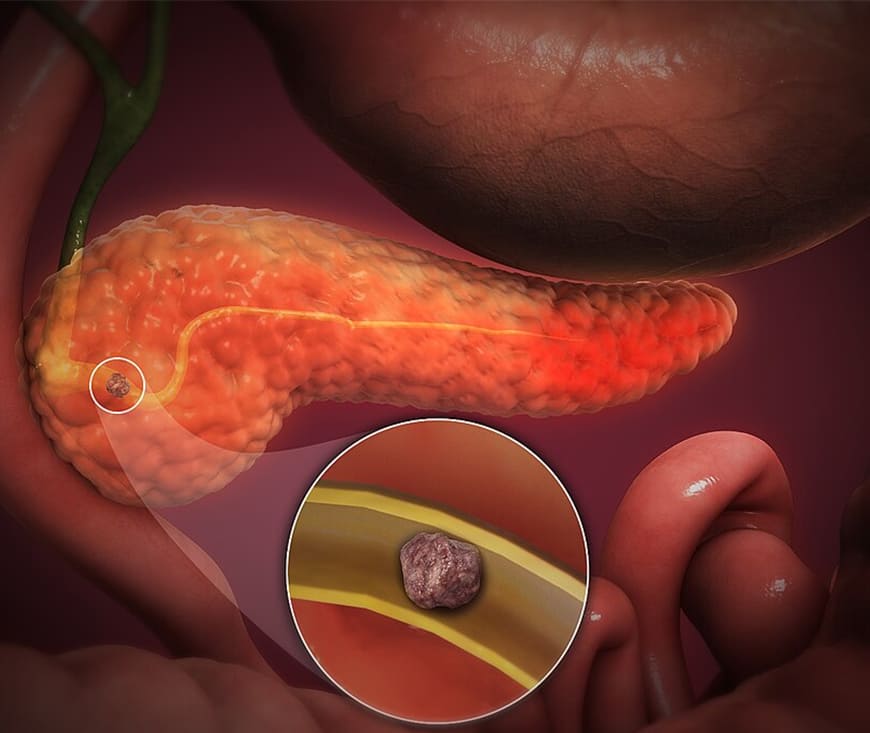

Pancreatitis is inflammation of the pancreas, often caused by gallstones, heavy alcohol

use, or high triglyceride levels. Acute pancreatitis requires hospitalization for

fluids, pain relief, and sometimes antibiotics. Chronic pancreatitis may involve enzyme

replacements, pain management, and lifestyle changes like a low-fat diet and avoiding

alcohol.